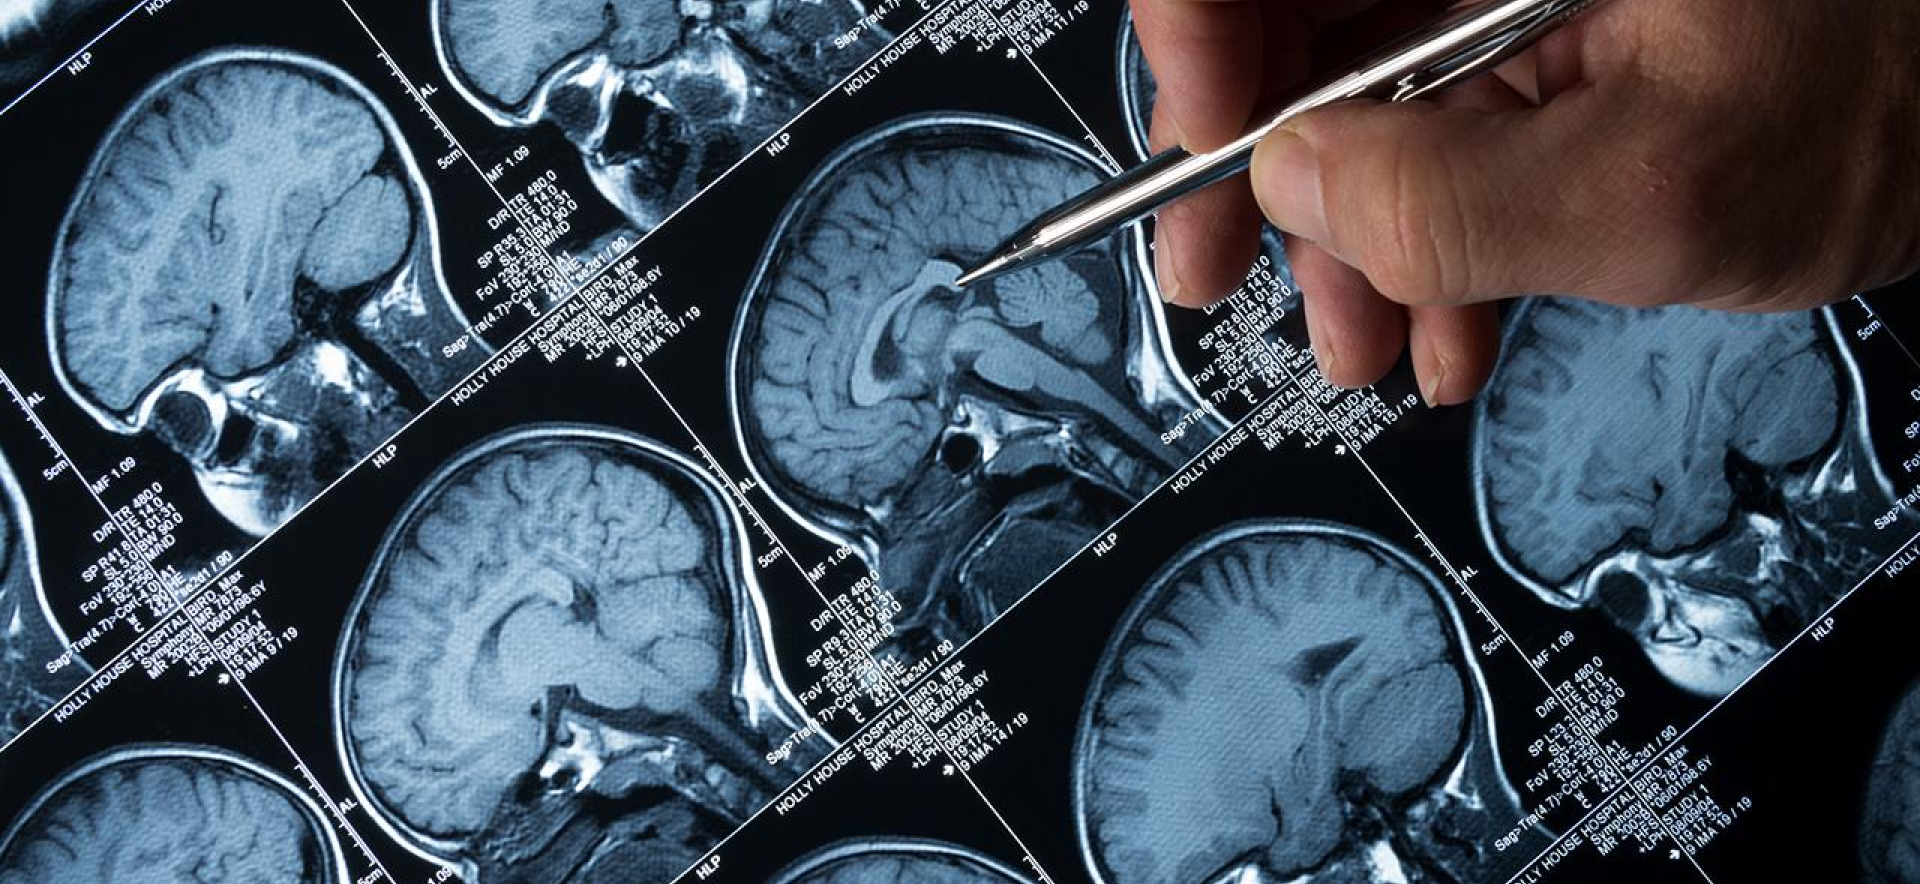

İngiltere, Alzheimer hastalığı ve diğer demans türlerinin daha erken teşhis edilmesine yönelik kan testlerini değerlendirmek üzere denemeler yapıyor. Bu adımın, bakım, destek ve yeni ilaç tedavilerine daha erken başlamak için kapıları açacağı umuluyor. Dünya genelinde 55 milyon insanın demansla mücadele ettiği bilinirken, bu rakamın 2050 yılında 139 milyona ulaşması bekleniyor.

Demans, birçok beyin hastalığının belirtisi olarak hafıza kaybı, davranış değişiklikleri ve kişilik değişimleri gibi semptomlarla kendini gösterir. Alzheimer, demansın en yaygın nedenlerinden biri olup hafıza kaybı genellikle ilk belirtidir.

Londra'daki University College Hastanesi'nde yürütülen denemelerde, miridesap adlı ilacın etkisi incelenmektedir. Bu denemeler, ilacın beyinde biriken amiloid adlı proteinin zararlı etkilerini engelleyebileceğini belirlemeyi hedeflemektedir.